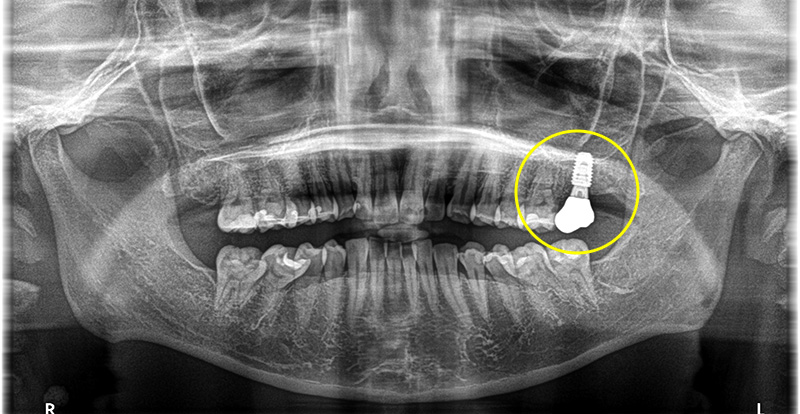

抜歯、膿や不良肉芽の掻把、骨造成、2回法でのインプラント体の埋入までを1回のオペで行い、その後定期的に経過観察をし、インプラントと骨が結合したことを確認できてから上部構造の型どり、セットまで行っています。

上部構造(人工歯)の装着・治療完了

術後は奥歯で硬いものもしっかりと噛むことができるようになり、機能的にも審美的にも大変満足していただいています。

現在は、骨造成を行ったことにより、術後も良く、ご自身でのセルフケアや、メインテナンスにてプロフェッショナルケアを定期的に行っており、現在もキレイな状態を保つことができています。